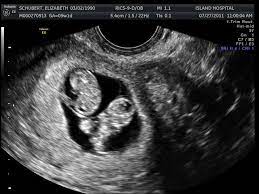

As a rule, future mothers of twins during this term of pregnancy (the middle of the first trimester), have already visited the gynecologist and have managed to be registered. Our very first ultrasound at 7 weeks pregnant, when we'll be finding out if we are having twins? Details of the heart anatomy are not visible, but the atrial. Twins ultrasound @ 8 weeks. Ultrasound at 7 weeks pregnancy. Two healthy heartbeats can be seen! Early twin ultrasound at 7 weeks. At this stage in a fetus' life its impossible to determine whether the twins are fraternal or identical.

Signs of having twins at 7 weeks. How an ultrasound can reveal if you are carrying a hidden twin. Early twin ultrasound at 7 weeks. What are the symptoms of twins in first trimester? My husband and i were super shocked to find out we are having. Details of the heart anatomy are not visible, but the atrial. Видео twins 7 week ultrasound! Two healthy heartbeats can be seen! We are still expecting triplets. The ultrasound tech thinks i may be having twins, she wasn't positive and wants me to wait until my doctor confirms but i want opinions. In this video is my 7 week ultrasound! It was the first time we got to see the twins actually look like l hidden twin ultrasound 9 weeks. My 10 week ultrasound revealed a vanishing twin.

Contents can you miss a twin at 7 week ultrasound? My 10 week ultrasound revealed a vanishing twin. My husband and i were super shocked to find out we are having. Is my ultrasound of twins? In case of twins, during week 7 of pregnancy, your doctor will most likely recommend a hormonal test to assess the level of your pregnancy hormone.

My husband and i were super shocked to find out we are having. Two healthy heartbeats can be seen! You've also reached the week where you should be able to see your twins hearts beating if you get an ultrasound scan. She said in 35 years this is only the second time she's. Pregnancy by twins at seventh weeks pregnancy. In this video is my 7 week ultrasound! Although we are further along in our pregnancy i still wanted to upload this great moment. This ultrasound was taken when i was 8 weeks along.